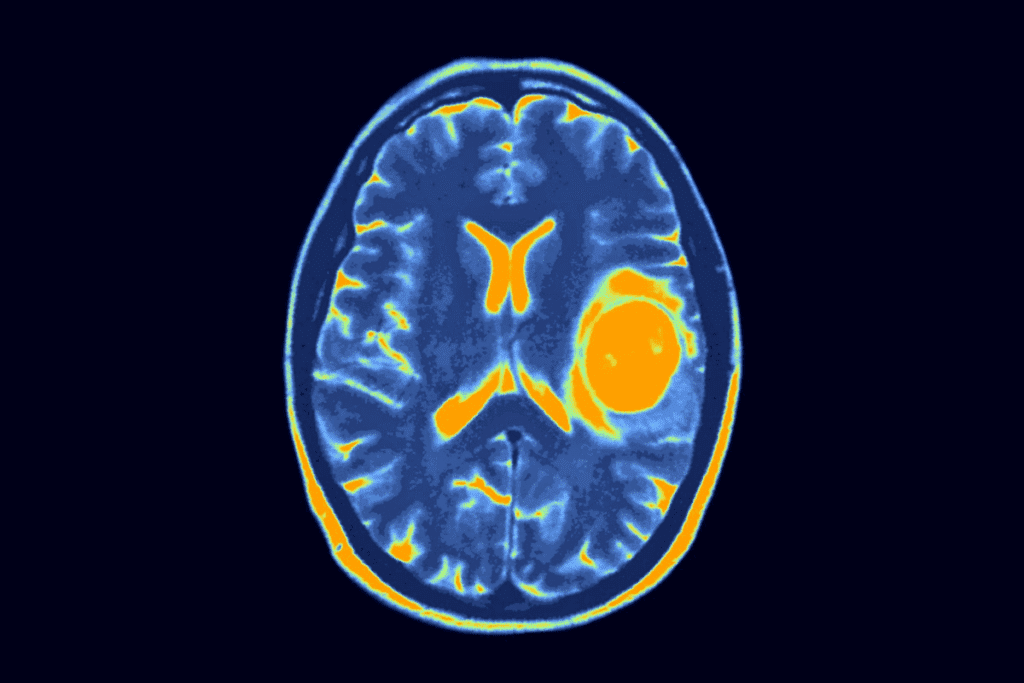

Imaging Techniques

Imaging is very important in diagnosing Wilms tumor. Ultrasound is often the first tool used. It’s non-invasive and helps find the tumor’s location and size.

Computed Tomography (CT) scans and Magnetic Resonance Imaging (MRI) are also used. They give detailed images of the tumor and its surroundings. This helps in planning the treatment.